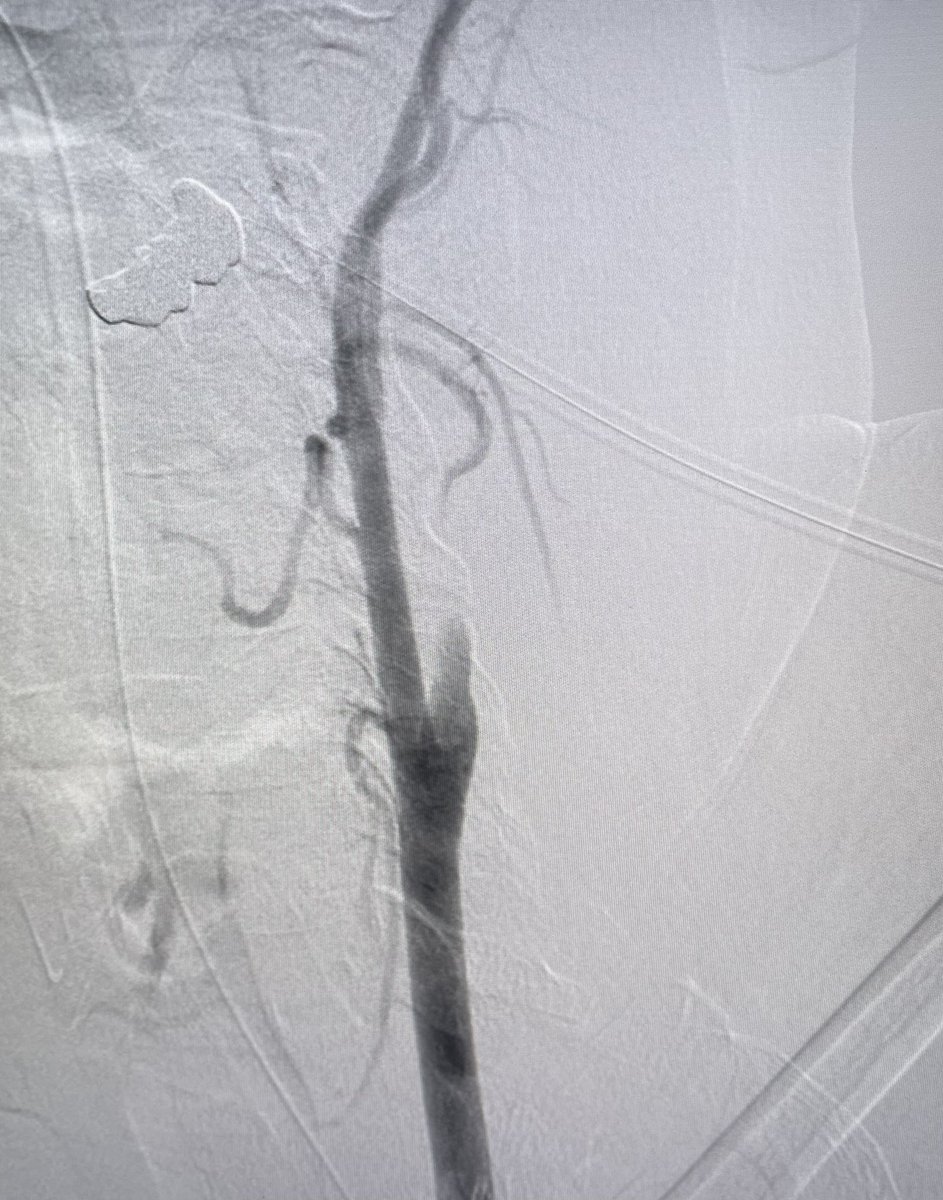

Dr.Amit Sahu is a Neuro & Vascular Interventional Radiologist in Lilavati, Apollo, Wockhardt, SLRaheja, Zen Hospitals in Mumbai offering endovascular treatments

Amit Sahu@MumbaiIR·

What’s happening?